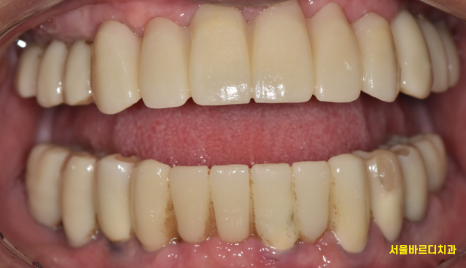

240904

짜잔~~

치료가 끝난 모습입니다.

약 9개월동안 치료를 진행하였네요.

1년은 안걸렸지만

계절이 3번이 바뀔동안

치과를 몇번이나 와주시고

약속 한번 어기지 않은 환자분께 감사함을 표합니다.